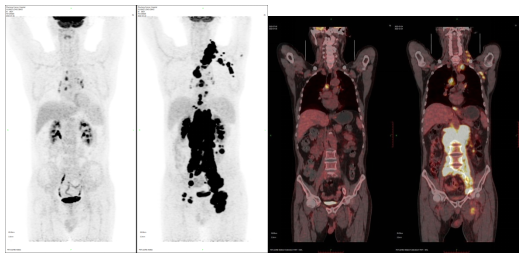

图2.PET-CT清晰直观地显示肿瘤治疗前后全身病灶对比